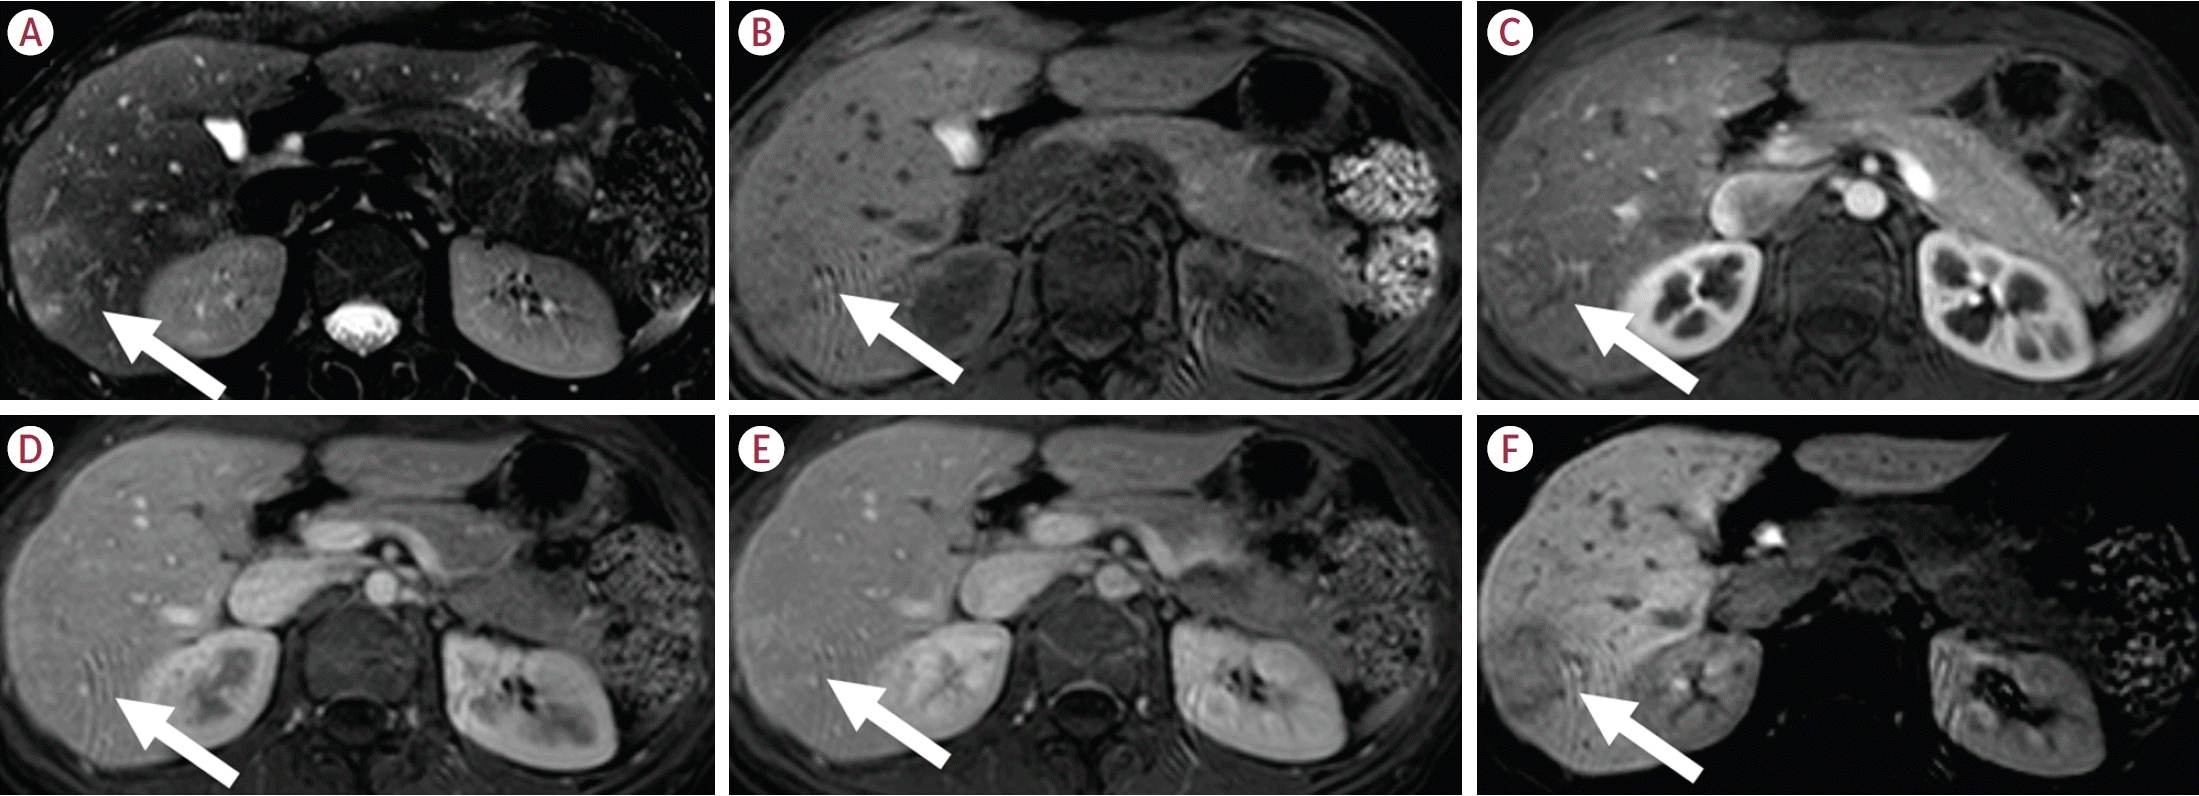

10. Tse JR, Naini BV, Lu DS, Raman SS. Qualitative and quantitative gadoxetic acid-enhanced MR imaging helps subtype hepatocellular adenomas. Radiology. 2016; 279:118–127.

11. Tse JR, Felker ER, Cao JJ, Naini BV, Liang T, Lu DSK, et al. Hepatocellular adenoma subtypes based on 2017 classification system: exploratory study of gadoxetate disodium-enhanced MRI features with proposal of a diagnostic algorithm. AJR Am J Roentgenol. 2023; 220:539–550.

12. Reizine E, Amaddeo G, Pigneur F, Baranes L, Legou F, Mulé S, et al. Quantitative correlation between uptake of Gd-BOPTA on hepatobiliary phase and tumor molecular features in patients with benign hepatocellular lesions. Eur Radiol. 2018; 28:4243–4253.

13. Reizine E, Ronot M, Ghosn M, Calderaro J, Frulio N, Bioulac-Sage P, et al. Hepatospecific MR contrast agent uptake on hepatobiliary phase can be used as a biomarker of marked β-catenin activation in hepatocellular adenoma. Eur Radiol. 2021; 31:3417–3426.

23. Kim TH, Woo S, Ebrahimzadeh S, McInnes MDF, Gerst SR, Do RK. Hepatic adenoma subtypes on hepatobiliary phase of gadoxetic acid-enhanced MRI: systematic review and meta-analysis. AJR Am J Roentgenol. 2023; 220:28–38.

32. Ba-Ssalamah A, Antunes C, Feier D, Bastati N, Hodge JC, Stift J, et al. Morphologic and molecular features of hepatocellular adenoma with gadoxetic acid-enhanced MR imaging. Radiology. 2015; 277:104–113.

33. Bise S, Frulio N, Hocquelet A, Alberti N, Blanc JF, Laurent C, et al. New MRI features improve subtype classification of hepatocellular adenoma. Eur Radiol. 2019; 29:2436–2447.

40. Glockner JF, Lee CU, Mounajjed T. Inflammatory hepatic adenomas: characterization with hepatobiliary MRI contrast agents. Magn Reson Imaging. 2018; 47:103–110.

48. Ueno A, Masugi Y, Yamazaki K, Komuta M, Effendi K, Tanami Y, et al. OATP1B3 expression is strongly associated with Wnt/β-catenin signalling and represents the transporter of gadoxetic acid in hepatocellular carcinoma. J Hepatol. 2014; 61:1080–1087.

50. Reizine E, Ronot M, Pigneur F, Purcell Y, Mulé S, Burgio MD, et al. Iso- or hyperintensity of hepatocellular adenomas on hepatobiliary phase does not always correspond to hepatospecific contrast-agent uptake: importance for tumor subtyping. Eur Radiol. 2019; 29:3791–3801.